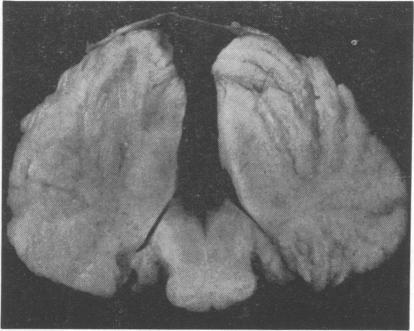

Two unique cases of the syndrome of absent abdominal muscles with central nervous system involvement are presented. Microcephaly, polymicrogyria, and cerebellar heterotopiae were present in both. In case 1 there was also absence of the corpus callosum and agenesis of the cerebellar vermis. In case 2 a count of anterior horn cells in the spinal cord showed a reduction of approximately 50% in the lower thoracic region. The pertinent literature is briefly discussed. The findings in the nervous system suggest that the syndrome is the result of defective embryogenesis during the first trimester.

本文报告了两例伴有中枢神经系统受累的腹直肌缺如综合征的独特病例。两例均存在小头畸形、多小脑回和小脑异位。病例1还存在胼胝体缺如和小脑蚓部发育不全。病例2脊髓前角细胞计数显示下胸段减少约50%。对相关文献进行了简要讨论。神经系统的发现表明,该综合征是孕早期胚胎发育缺陷的结果。